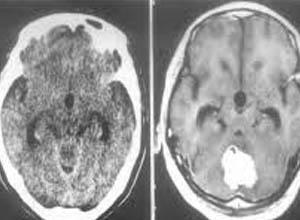

脑瘤检查报告图片,脑瘤检查报告单图片

受害者的急诊ct报告(图片来自京华时报微博)

脑瘤检查报告单图片

脑瘤ct检查报告图片

脑瘤ct报告单图片

脑瘤拍片图片

脑瘤早期ct图片大全